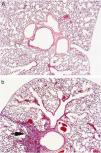

La puntuación fue reproducible con una concordancia elevada entre observadores (r2=0,99; p<0,001). Todos los ratones sensibilizados a la ovalbúmina, tanto los tratados con rofecoxib como aquéllos sin tratar, desarrollaron una respuesta inflamatoria, mientras que los animales no sensibilizados que se utilizaron como controles en la evaluación histológica no manifestaron signos de inflamación (fig. 2). Los eosinófilos y las células mononucleares eran predominantes en las zonas perivascular y peribronquial de los pulmones inflamados. La inflamación se manifestó por lo general como acumulaciones focales de células inflamatorias alrededor de las estructuras broncovasculares, pero ocasionalmente también se observaron células diseminadas. En la figura 3 se ilustra el grado de inflamación de los ratones sensibilizados a la ovalbúmina sin tratar y los tratados con rofecoxib, cuantificada según el sistema de puntuación descrito anteriormente. Se observó una tendencia (p=0,09) hacia puntuaciones más elevadas en los animales tratados con rofecoxib; sin embargo, la diferencia entre los ratones tratados y sin tratar no fue significativa. Un resultado análogo se obtuvo en el recuento de eosinófilos por milímetro cuadrado (área de la sección histológica): se observó una media de 6,22±2,0células/mm2 en los animales tratados con placebo y de 10,69±3,47células/mm2 en los tratados con rofecoxib (p=0,2). Por último, se observó una correlación significativa entre la respuesta de las vías respiratorias a 100mg/ml de metacolina y el grado de inflamación en los ratones sensibilizados (fig. 4) (r2=0,38; p=0,019).

Microfotografías de las vías respiratorias bajas de los ratones no sensibilizados (a) y sensibilizados sin tratar (b). Los animales sin sensibilizar no mostraron ningún signo de inflamación, mientras que los sensibilizados presentaban acumulaciones focales de células inflamatorias alrededor de las estructuras broncovasculares (flecha). El infiltrado se componía en gran parte de células mononucleares, con un número elevado de eosinófilos. Las imágenes son representativas de observaciones procedentes de los grupos estudiados.